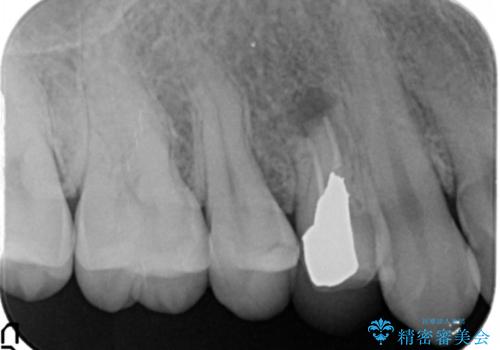

根の詰め物をした後も歯ぐきからウミが出てくる上に、咬むと痛いとのことでした。

さらに、同じ病院で根の先を切る手術も行なったが症状が改善しなかったそうです。

前回の治療がうまくいかなかった原因として、根の中がまだ汚い状態で、根の先だけを切ってもうまくいかない可能性があったことを説明し、根管治療をやり直すことになりました。

なお、根管充填にはMTAを使用しました。

術後は瘻孔、圧痛、打診痛も消失し、根尖病変の縮小もみられました。経過良好です。